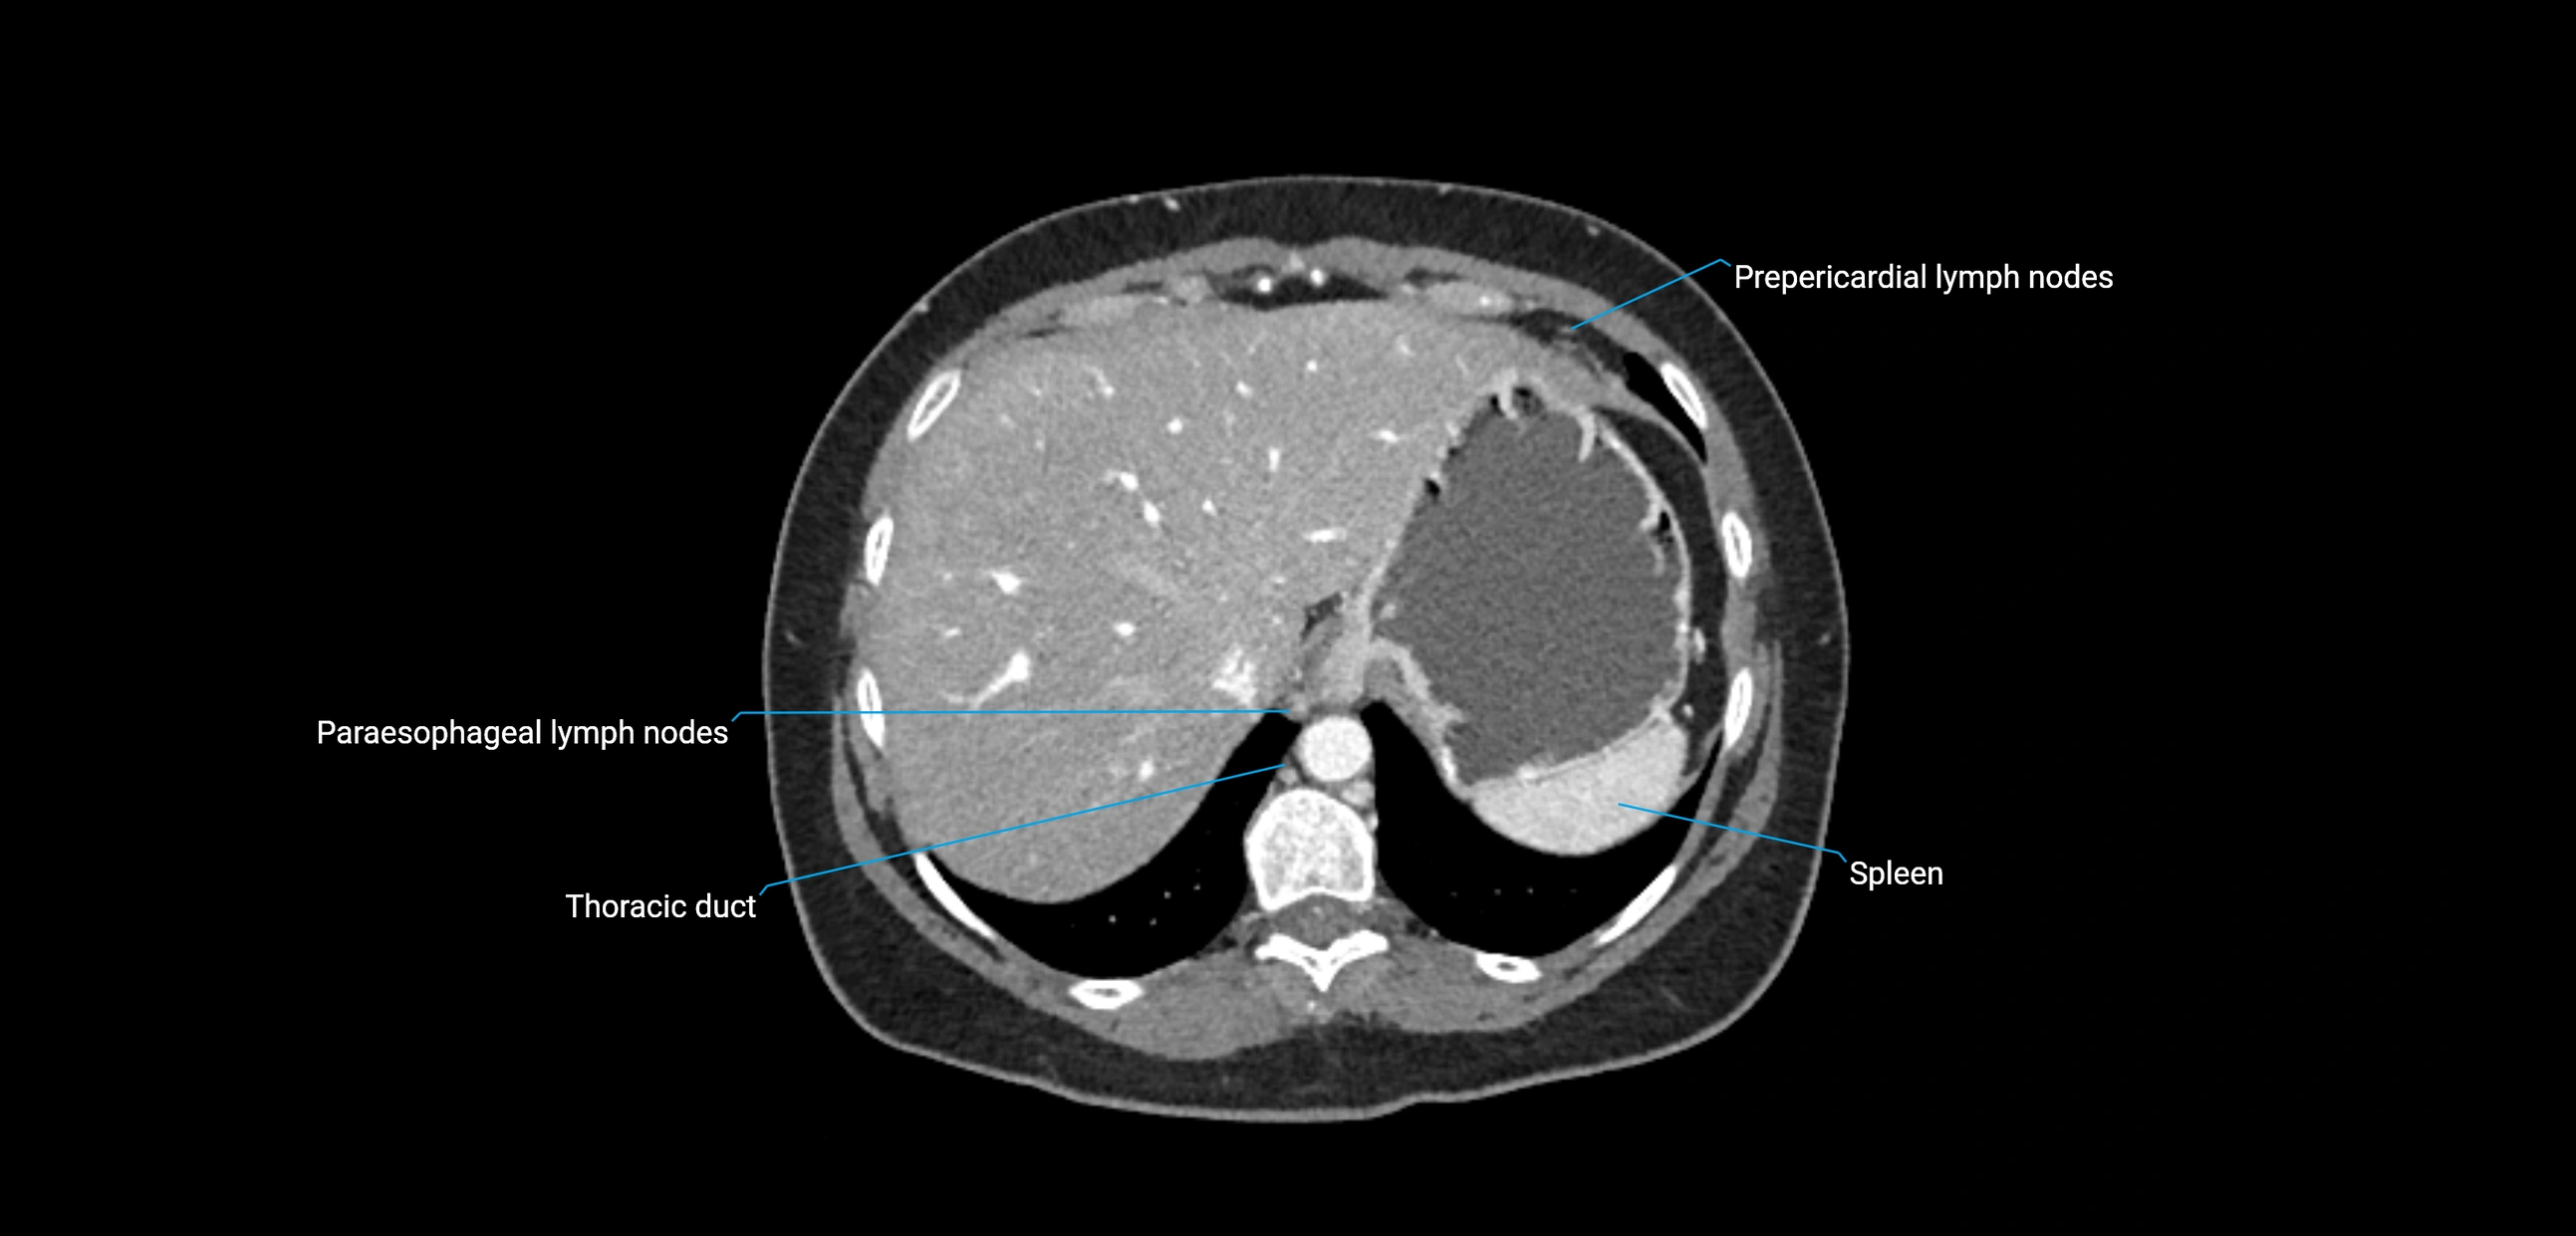

MRI images

image